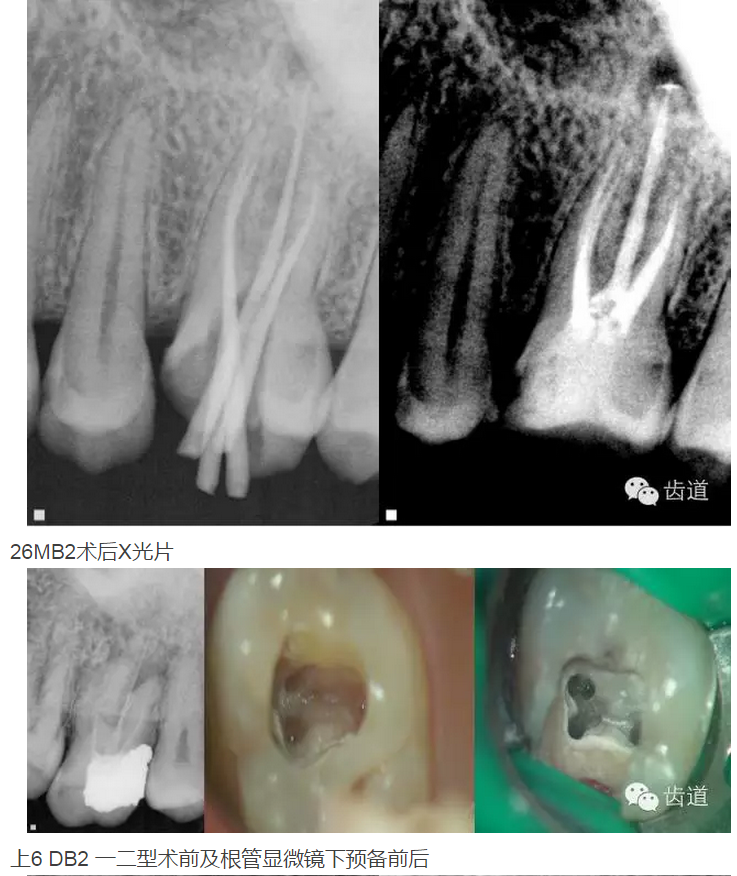

上頜第一磨牙:多為3-4個(gè)根管,MB2發(fā)生率約為60%;

上頜第二磨牙:與上頜第一磨牙相似,多為3根管,偶見雙鄂根管;